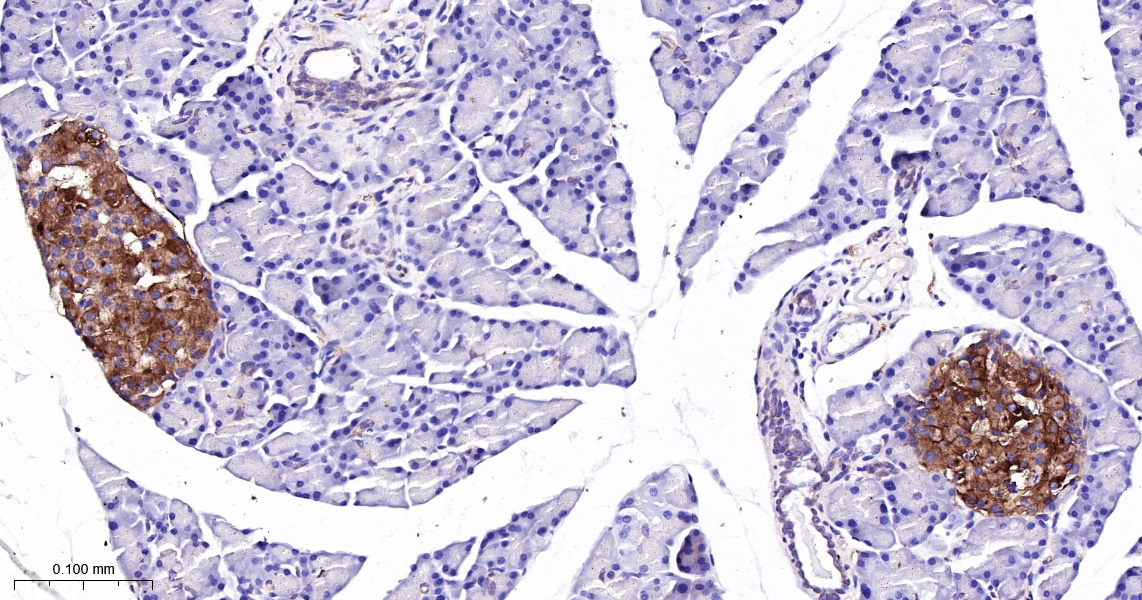

PRNP Recombinant Antibody

• IHC

Product Name PRNP Recombinant Antibody

Applications WB, FCM, IF(ICC), IHC

IHC